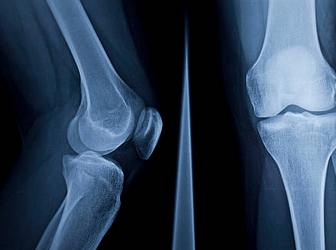

무릎 연골 찢어짐 증상 원인 치료방법 수술비용 등 총 정리해드리도록 하겠습니다. 무릎 연골 찢어짐은 무릎 관절에 있는 연골이 부상이나 나이로 인해 손상되는 경우를 말합니다. 연골은 뼈와 뼈 사이에 있는 연한 조직으로, 뼈의 마찰을 줄여주고 충격을 흡수하는 역할을 합니다.

3. 운동 제한: 무릎 연골 찢어짐은 무릎 관절의 움직임을 제한합니다. 연골이 손상되면 관절의 원활한 작동이 방해되고, 뼈가 서로 부딪치거나 걸리는 현상이 발생할 수 있습니다. 이러한 현상은 무릎을 굽히거나 펴거나 돌리는 것이 어렵게 만들고, 걷거나 달리거나 계단을 오르내리는 것과 같은 일상적인 활동에도 어려움을 겪게 할 수 있습니다.

무릎 연골 찢어짐의 수술적 치료는 크게 절제술과 재건술로 나뉩니다. 절제술은 손상된 연골을 제거하는 방법으로, 수술 시간이 짧고 회복이 빠른 장점이 있습니다. 하지만 제거된 연골은 다시 자라지 않으므로 장기적으로 관절염의 위험이 증가합니다. 재건술은 손상된 연골을 복구하거나 이식하는 방법으로, 자신의 연골 조각이나 타인의 연골 조각, 인공 연골 등을 사용할 수 있습니다. 이 방법은 장기적으로 관절 건강을 유지할 수 있는 장점이 있지만, 수술 시간이 길고 회복이 오래 걸리는 단점이 있습니다.